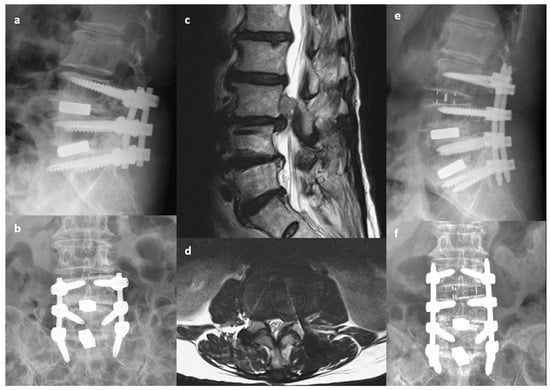

Figure 1.

A 78-year-old woman with low back pain and right thigh radiation. Primary transforaminal lumbar interbody fusion was performed 3 years previously to treat spinal stenosis and disc herniation at L4-5-S1. (a,b) Preoperative X-ray indicating decreased disc height at L3-4. (c,d) Preoperative MRI indicating uncontained disc extrusion with upper migration at L3-4. (e,f) Postoperative X-ray indicating oblique lumbar interbody fusion at L3-4 with extension of posterior instrumentation to L3. Left-side laminotomy of L3 was performed to remove the migrated disc.